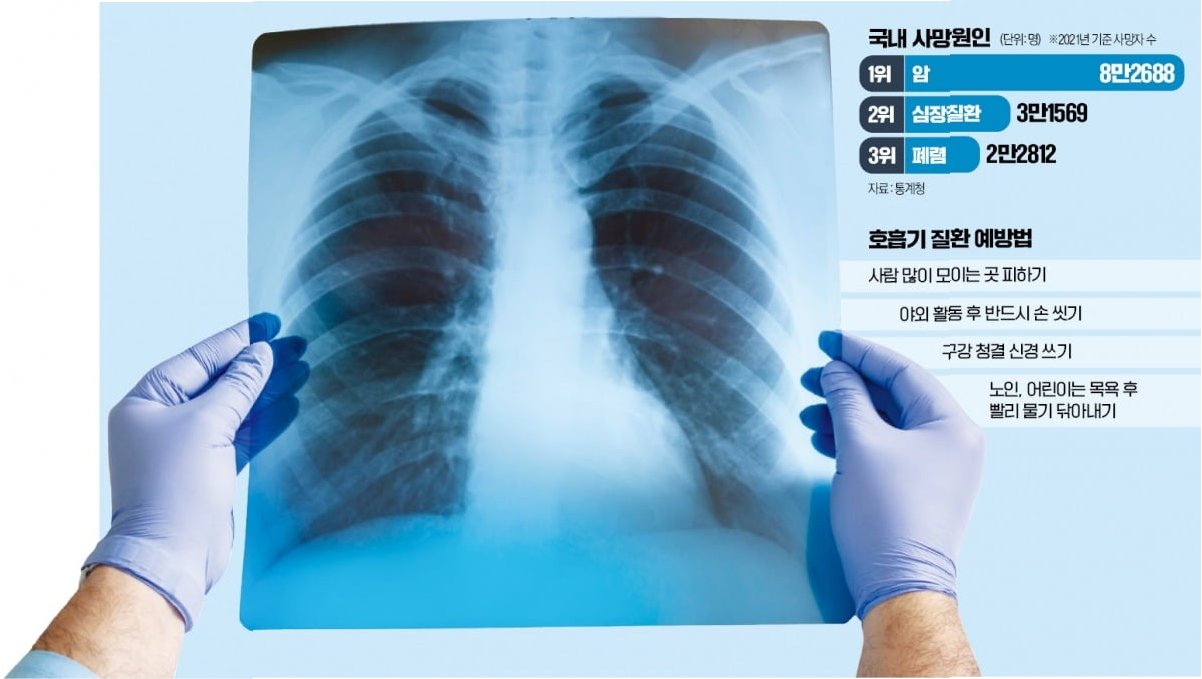

폐렴, 연령에 따라 달라지는 양상

폐렴은 폐에 염증이 생기는 질환으로, 연령대에 따라 그 양상과 위험도가 크게 달라집니다. 고령층과 젊은층의 폐렴은 발병 원인, 증상, 치료 과정, 예후 등 여러 측면에서 차이를 보입니다. 특히 고령층은 면역력이 약하고 만성 질환을 동반하는 경우가 많아 폐렴에 더욱 취약합니다. 젊은층은 상대적으로 건강하지만, 특정 원인균에 노출되거나 과도한 스트레스, 흡연 등으로 인해 폐렴에 걸릴 수 있습니다. 이 글에서는 고령층과 젊은층의 폐렴을 비교 분석하여 각 연령대에 맞는 예방 및 관리 방법을 제시하고자 합니다.

예방, 폐렴으로부터 당신을 지키는 열쇠

폐렴은 예방이 매우 중요합니다. 고령층은 폐렴구균 백신, 인플루엔자 백신 접종을 통해 폐렴 발생 위험을 줄일 수 있습니다. 또한, 구강 위생 관리를 철저히 하고, 규칙적인 식사와 운동을 통해 면역력을 강화해야 합니다. 흡인성 폐렴 예방을 위해, 식사 시에는 앉아서 천천히 먹고, 음식물을 삼키기 어려울 경우 전문가와 상담하여 적절한 조치를 취해야 합니다. 젊은층은 개인 위생 관리를 철저히 하고, 감염 위험을 줄이기 위해 마스크 착용, 손 씻기 등을 생활화해야 합니다. 충분한 휴식과 수면을 취하고, 스트레스를 관리하며, 금연하는 것이 중요합니다. 건강한 식습관과 규칙적인 운동을 통해 면역력을 강화하는 것도 폐렴 예방에 도움이 됩니다.